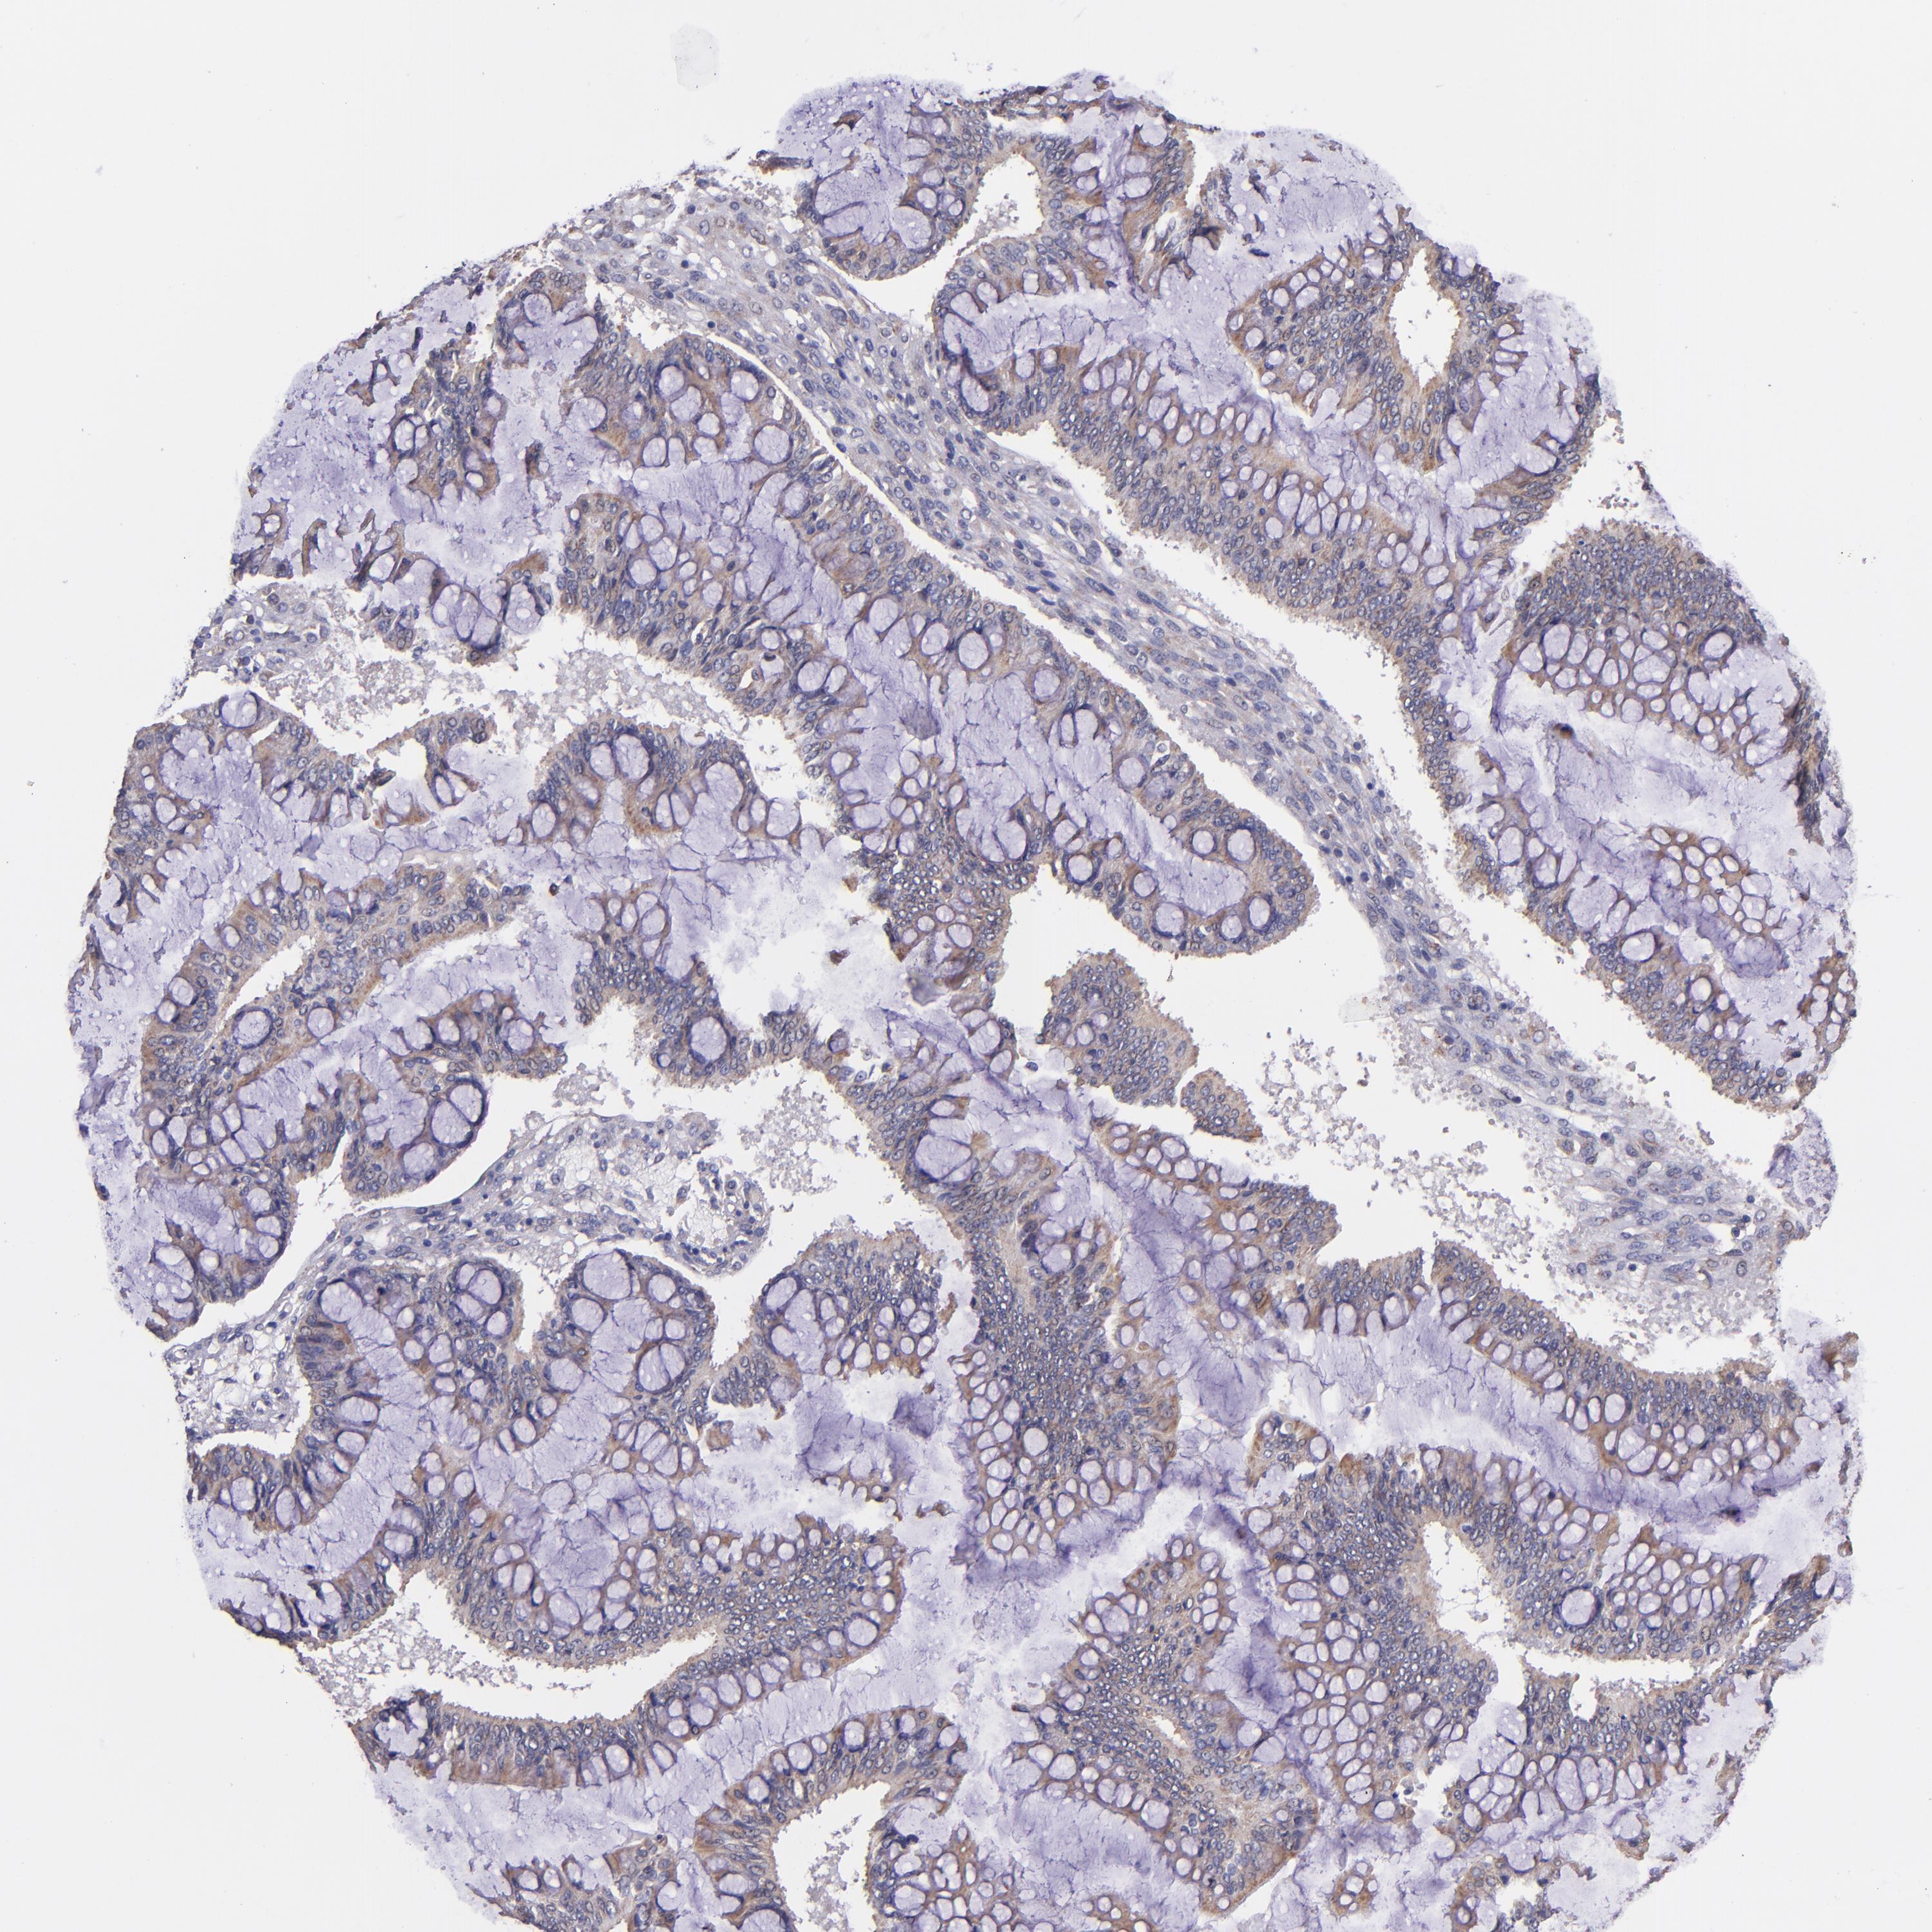

OVARIAN CANCER - Protein expressioni

A mouse-over function shows sample information and annotation data. Click on an image to view it in a full screen mode. Samples can be filtered based on level of antibody staining by selecting one or several of the following categories: high, medium, low and not detected. The assay and annotation is described here.

Note that samples used for immunohistochemistry by the Human Protein Atlas do not correspond to samples in the TCGA dataset.

Antibody stainingi

Antibody staining in the annotated cell types in the current human tissue is reported as not detected, low, medium, or high, based on conventional immunohistochemistry profiling in selected tissues. This score is based on the combination of the staining intensity and fraction of stained cells.

Each image is clickable and will lead to virtual microscopy that enables deeper exploration of all samples and also displays staining intensity scores, fraction scores and subcellular localization as well as patient and tissue information for each sample.

Antibody CAB016305

Cystadenocarcinoma, serous, NOS

Cystadenocarcinoma, mucinous, NOS

Carcinoma, endometroid

Carcinoma, NOS